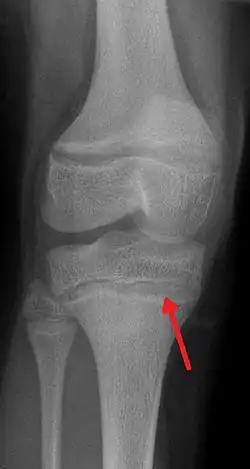

An X ray demonstrating the characteristic finding of lead poisoning in humans—dense metaphyseal lines.

One of the clinical signs of rickets that doctors look for is cupping and fraying at the metaphyses when seen on X-ray.